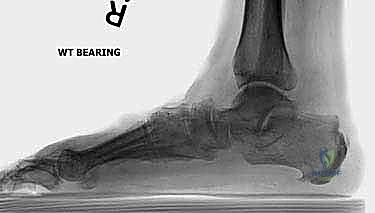

3. التصوير الشعاعي (X-rays): صور أشعة سينية أثناء الوقوف (Weight-bearing) لتقييم زوايا العظام ودرجة انهيار المفاصل.